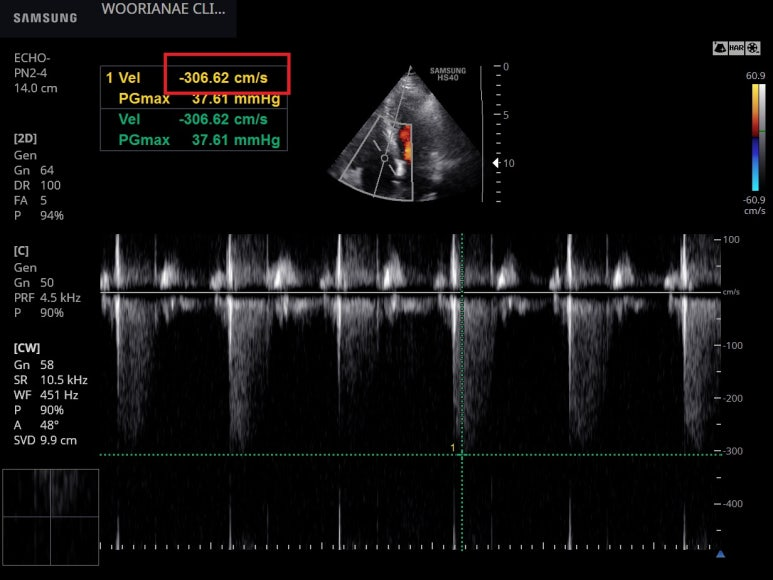

수동 혈압 측정시 불규칙한 맥박이 의심되어 확.. : 네이버블로그 상기 환자 2월에 심초음파 이 당시도 심전도에서 심방세동 상태 다른 소견은 없으나 좌심방의 AP diameter는 3.93 cm, volumn은 54.3 ml/m2 으로 부피...